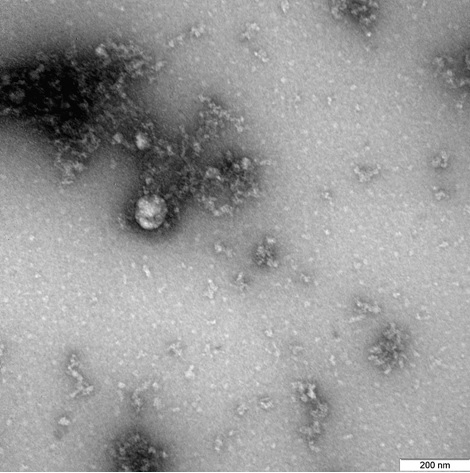

Вчені Новосибірського наукового інституту «Вектор» «Роспотребнадзора» вперше в світі отримали знімки нового штаму коронавірусу, який був виявлений на початку грудня у Великій Британії. Як повідомляється на сайті відомства, вірус був виділений від пацієнта в грудні минулого року.

Знімок був отриманий за допомогою трансмісійного електронного мікроскопа при 100000-кратному збільшенні. На ньому можна побачити вірусну частку округлої, трохи плеоморфної форми близько 140 нанометрів і типовими для коронавірусу колбоподібними пепломерами (спікулами) довжиною близько 20 нанометрів.